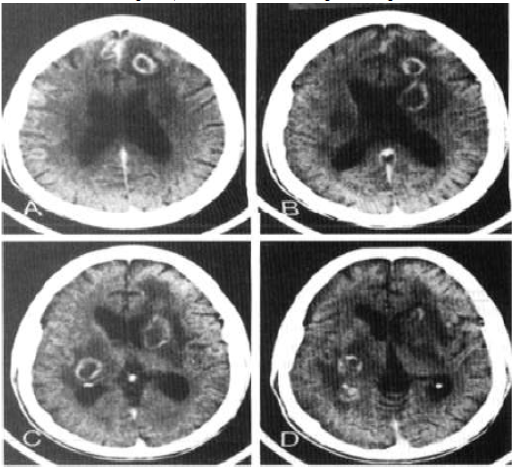

Sr. FS, 39 anos, convive com HIV há 10 anos, faz uso irregular de terapia antirretroviral e não sabe referir seu último

CD4 dosado. Ele procura atendimento no pronto-socorro por quadro de rebaixamento do nível de consciência há três

dias, associado à intensa cefaleia. Apresentou três episódios de convulsões tônico-clônicas generalizadas. O exame

neurológico simplificado demonstrou hemiparesia à esquerda, Glasgow 13, sem sinais de irritação meníngea e com

fundo de olho normal. Foi realizada tomografia, de acordo com a imagem a seguir:

Considere que a principal hipótese diagnóstica foi confirmada. Qual deve ser a conduta CORRETA?

Considere que a principal hipótese diagnóstica foi confirmada. Qual deve ser a conduta CORRETA?